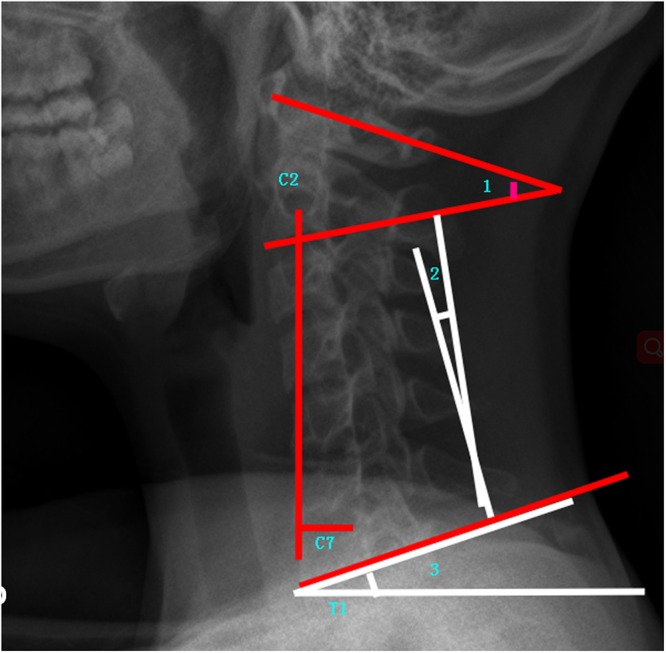

Cervical sagittal alignment parameters: C1-C2 (C1-C2 cervical lordosis, the angle between C1 and the caudal endplate of C2), CL (C2-C7 cervical lordosis is the angle between the caudal endplate of C2 and the caudal endplate of C7), cSVA(cSVA is the horizontal offset from the plumbline dropped from C2 to the posterosuperior corner of C7), TS-CL (T1 Slope minus CL is the difference between T1 Slope and CL) (Fig. 2).

Figure 2.

Demonstrated cervical sagittal alignment parameters (1:C1-C2, 2:C2-C7, and 3: T1 Slope).